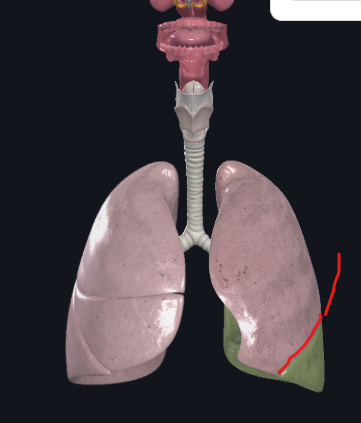

What structure is this?

Diaphragm

What structure is this?

Oblique fissure of right lung

What structure is this?

Oblique fissure of left lung